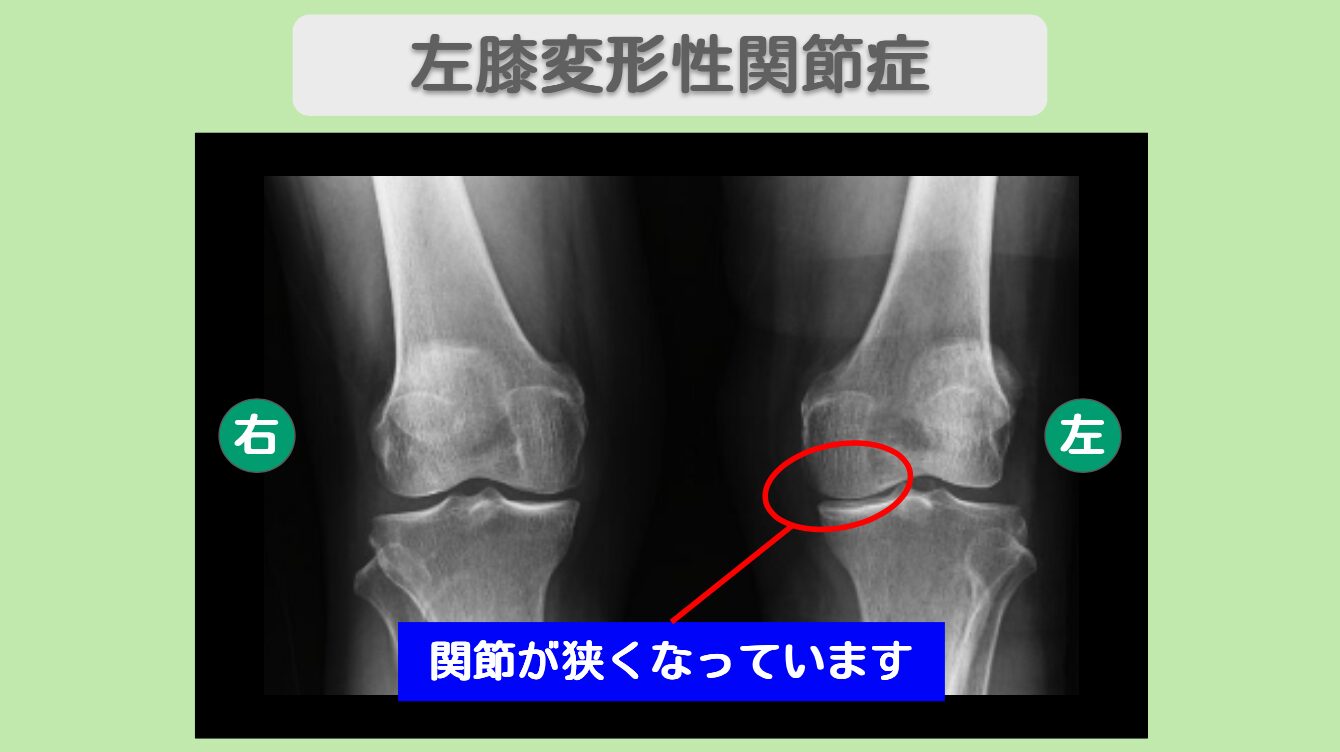

レントゲン所見

レントゲンにて左膝関節の狭小化を認めます